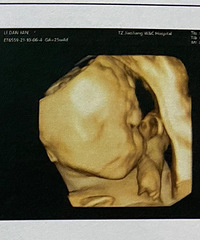

预产期:2023年5月20日建卡医院:温岭市妇幼保健院产检医院:温岭市妇幼保健院胎宝宝小名:还没取呢生产医院:未定哦B超照片/孕期相关照片一张